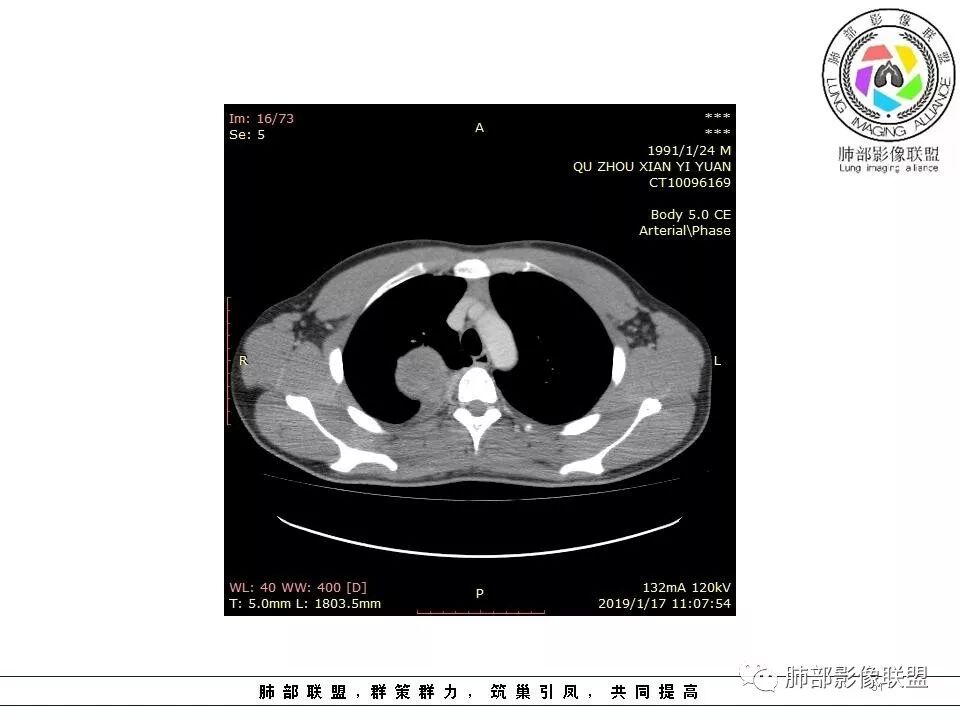

结果:神经纤维瘤

徐超:

后纵膈

术中确认就是纵膈

s100强阳性,还是提示神经来源

梭形一般不一定都是神经,但免疫组化s100+梭形细胞就强烈提示神经

神经纤维瘤也比较少

神经纤维瘤是比较少见,我在我们这证实的第一次见

神经纤维瘤来自椎管神经

脊椎椎管里的肿瘤,神经纤维瘤,神经鞘瘤很多啊

只是这个跑到椎管外去了